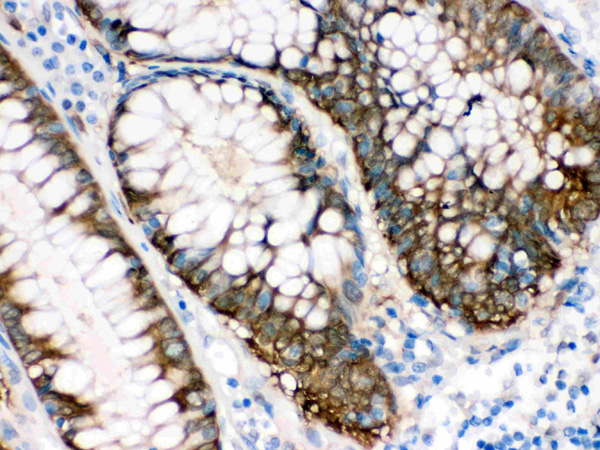

IHC (Immunohistochemistry)

(Figure 4. IHC analysis of IDH1 using anti-IDH1 antibody (AAA46338).IDH1 was detected in paraffin-embedded section of Human Intestinal Cancer Tissue. Heat mediated antigen retrieval was performed in citrate buffer (pH6, epitope retrieval solution) for 20 mins. The tissue section was blocked with 10% goat serum. The tissue section was then incubated with 1ug/ml rabbit anti-IDH1 Antibody (AAA46338) overnight at 4 degree C. Biotinylated goat anti-rabbit IgG was used as secondary antibody and incubated for 30 minutes at 37 degree C. The tissue section was developed using Strepavidin-Biotin-Complex (SABC) with DAB as the chromogen.)